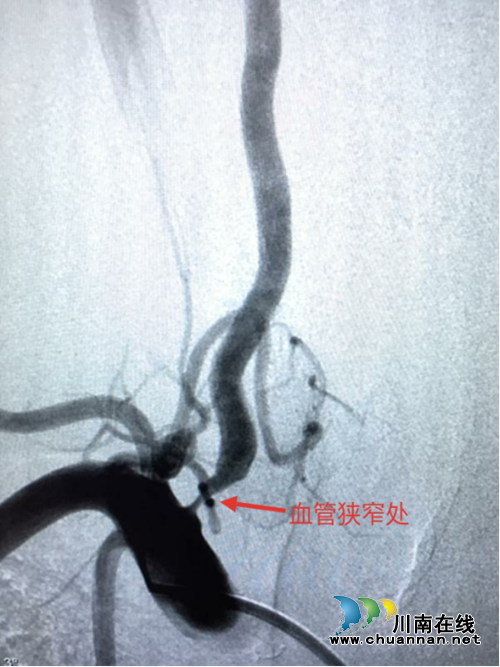

经过精心准备,9月27日,手术如期进行。医生们首先进行脑血管造影,了解狭窄血管的情况,制定手术方案。造影提示:右侧椎动脉起始部位狭窄率约85%。经过准确测量,选用5.0×15mm的椎动脉支架,经过导引导丝的引导,准确将支架置入狭窄血管处,经过扩张、释放,支架准确的将狭窄血管打开,造影显示血流恢复。手术历时1小时左右顺利结束。

支架置入前